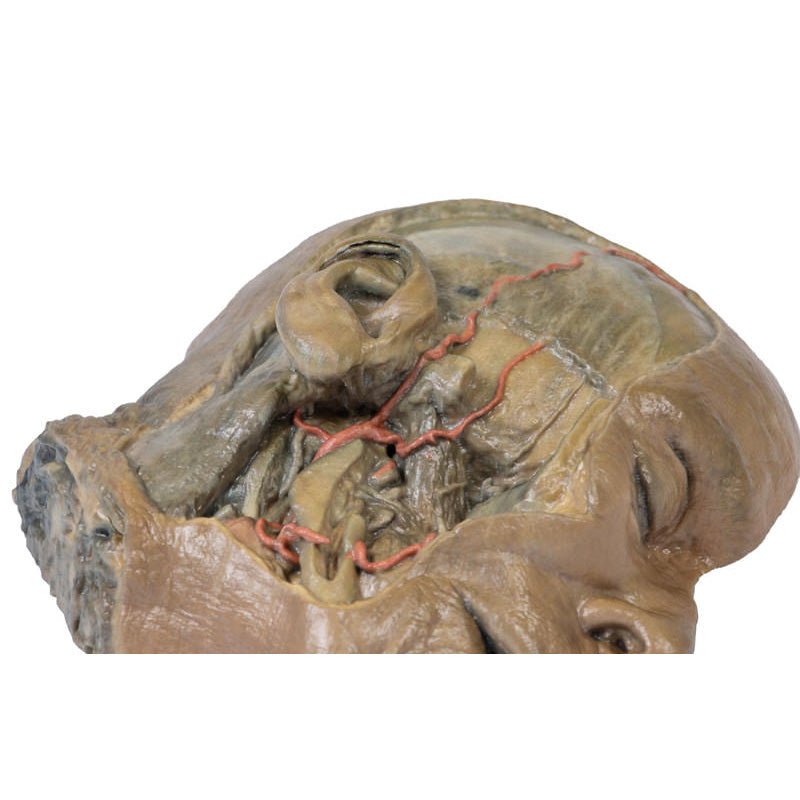

On the opposing side of the model, a superficial and deep dissection has

opened a large window into the anatomy of the lateral scalp and infratemporal

fossa. Across the scalp there is a well preserved posterior auricular nerve

and superficial temporal artery highlighted on the superficial surface of the

temporalis muscle. Anteriorly, the temporalis has been dissected to expose

the deep temporal arteries arising from across the maxillary artery.

The deep level of dissection has exposed parts of the infratemporal fossa

(through partial removal of the mandibular ramus and corpus) and dissection

of retromandibular tissues. At the inferior margin of the dissection window,

the cut edge of the retromandibular vein lies adjacent to the submandibular

gland and the ascending path of the facial artery as it cross towards to angle

of the mouth. Just superior to the cut retromandibular vein is the posterior

belly of the digastric muscle, overlying a small exposure of the deeper

internal jugular vein.

Just posterior to the retained ascending ramus of the mandible are the

external carotid artery and the occipital artery (running in parallel prior

to passing posteriorly). Tracing the external carotid artery superiorly, the

posterior auricular artery, superficial temporal artery, and maxillary artery are

all visible. The maxillary artery passes deep to the lateral pterygoid muscle

and into the infratemporal fossa, reappearing superior to the lateral pterygoid

as it passes into the pterygomaxillary fissure. Along its course, it gives rise

to the posterior deep temporal artery, the inferior alveolar artery (which is

exposed in the dissected mandibular corpus), the anterior deep temporal

artery, and the posterior superior alveolar artery. Finally, the inferior alveolar

nerve can be seen coursing within the opened mandibular corpus, and the

lingual nerve resting on the medial pterygoid. The buccinator muscle is also

retained, with the distal part of the parotid duct preserved as it enters the

muscle towards the oral mucosa